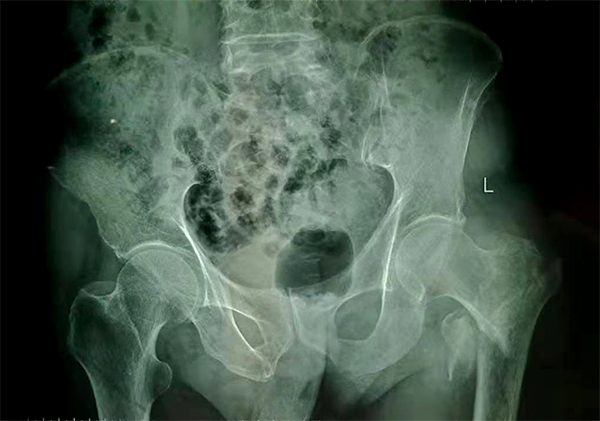

經(jīng)檢查拍片診斷為左股骨粗隆間粉碎性骨折,收入骨科住院,張爺爺既往有“2型糖尿病”病史10余年,還有“腦梗塞”病史5年,導(dǎo)致左側(cè)肢體偏癱。

手術(shù)前

手術(shù)后

9月10日上午,骨科順利完成張爺爺?shù)淖蠊晒谴致¢g骨折髓內(nèi)釘內(nèi)固定術(shù)。手術(shù)過程中麻醉平穩(wěn),術(shù)中出血量少,骨折手術(shù)時間持續(xù)一個多小時。